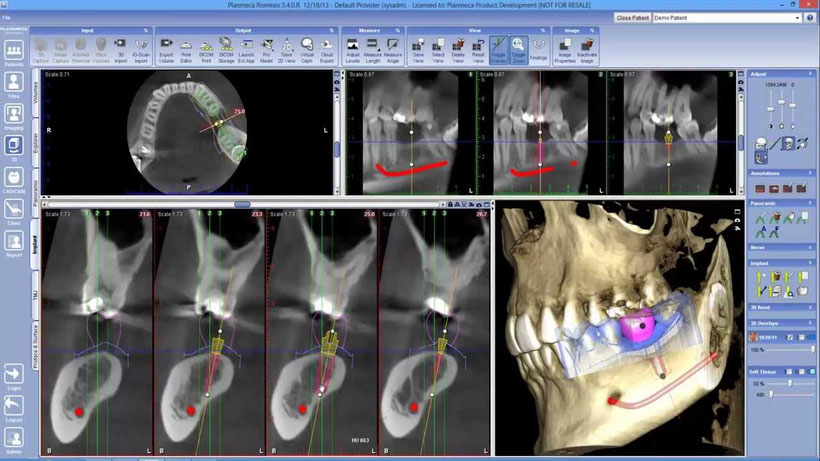

Es una técnica exploratoria radiográfica de muy baja radiación, que permite obtener imágenes radiológicas detalladas en tres dimensiones de una sección o plano de los maxilares junto a los tejidos blandos y estructuras anexas. Para este procedimiento se usa un tomógrafo CBT/CONE BEAM, cuando el uso de rayos X convencional no es suficiente para abarcar todas las estructuras de interés.

Este tipo de tomografías está indicada para el diagnóstico de trastornos óseos y dentales, como tumores, fracturas, trastornos de la articulación temporo mandibular, procesos infecciosos, etc.

También nos sirven para guiar procedimientos quirúrgicos como planificación de implantes, cirugías mayores y menores.

El especialista le solicitará una tomografía axial computarizada para planificar minuciosamente el tratamiento antes de llevarlo a cabo.

Esta técnica se realiza en un centro especializado en tomografías donde se pedirá al paciente que se mantenga de pie totalmente quieto, mientras coloca su cabeza en el equipo de rayos X y el detector gira alrededor de él en 360°. El paciente no puede llevar ningún tipo de objeto metálico en la cabeza ya que este puede alterar las imágenes de la tomografía, por lo cual deberá retirarse prótesis, joyas etc., durante el procedimiento. La radiación que se emite es mínima para el paciente, sin embargo, está contraindicado en mujeres embarazadas.